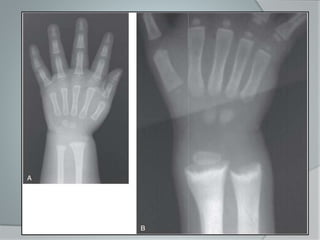

Radiología

 Los cambios raquíticos se visualizan

con mayor facilidad en los Rayos X

posteroanteriores de muñeca.

 Disminución de la opacidad de las

metafisis. (imagen de doble contorno)

con una cortical que apenas destaca.

 (Nelson) metafisis de aspecto

deshilachado

 En la radiografía del carpo, aumento

del espacio entre los extremos distales

del cubito y radio con los

metacarpianos.

 Retraso en la aparición de los puntos

de osificación

Radiología  Loscambios raquíticos se visualizan con mayor facilidad en los Rayos X posteroanteriores de muñeca.  Disminución de la opacidad de las metafisis. (imagen de doble contorno) con una cortical que apenas destaca.  (Nelson) metafisis de aspecto deshilachado

Radiología  Enla radiografía del carpo, aumento del espacio entre los extremos distales del cubito y radio con los metacarpianos.  Retraso en la aparición de los puntos de osificación